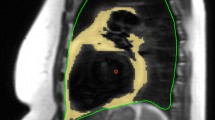

Epicardial and intra-myocardial fat quantification

Fat measurement was performed following segmentation of the Dixon data into fat and water images (Fig. 2) [15]. Intra-myocardial fat was quantified using a hand-drawn ROI covering the myocardial septum in the 4CH view, with care taken to avoid partial volume effects (Fig. 2a). Epicardial fat was quantified blindly between patients and controls by segmenting cardiac volumes and Dixon fat images using Kmeans clustering by a semiautomatic program implemented in python and Paraview (Fig. 2). The volumes of the cluster corresponding to the adipose tissue were then calculated to define an absolute fat volume, which is then divided by the whole heart volume to obtain a 3D MRI Dixon adipose fraction. In order to normalize the volume of epicardial fat present by body size, absolute fat volume was indexed to BSA.